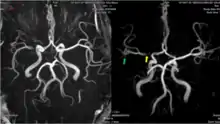

The leptomeningeal collateral circulation (also known as leptomeningeal anastomoses or pial collaterals) is a network of small blood vessels in the brain that connects branches of the middle, anterior and posterior cerebral arteries (MCA, ACA, and PCA),[1] with variation in its precise anatomy between individuals.[2] During a stroke, leptomeningeal collateral vessels allow limited blood flow when other, larger blood vessels provide inadequate blood supply to a part of the brain.[3]

Inter-territorial end to end anastomoses exist between branches of the anterior cerebral artery and middle cerebral artery, the posterior cerebral artery and middle cerebral artery, the anterior cerebral artery and posterior cerebral artery, and the right and left anterior cerebral arteries.[7][8][9][10] Intra-territorial anastamoses connect adjacent arterial branches within the same arterial territory (between two branches of the same middle cerebral artery, for example).[5]